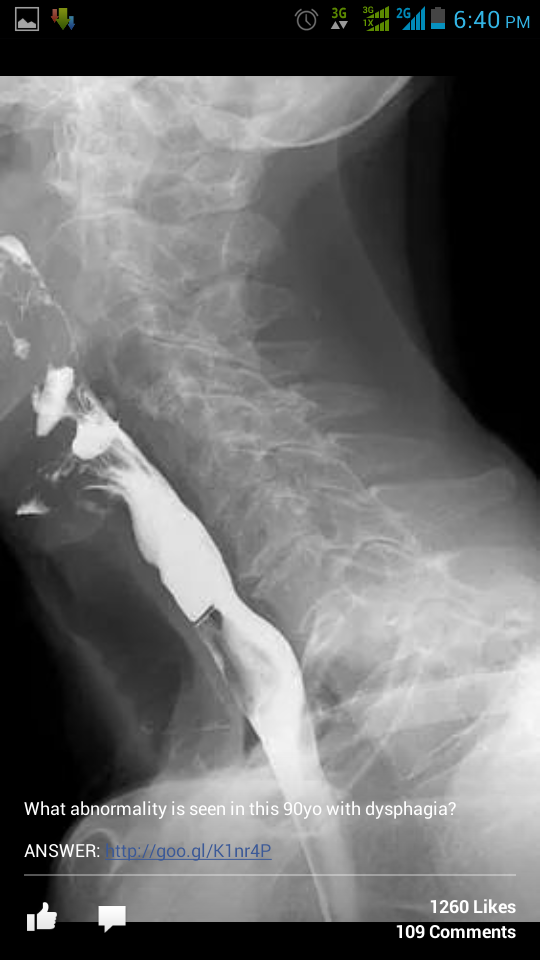

X rays collection